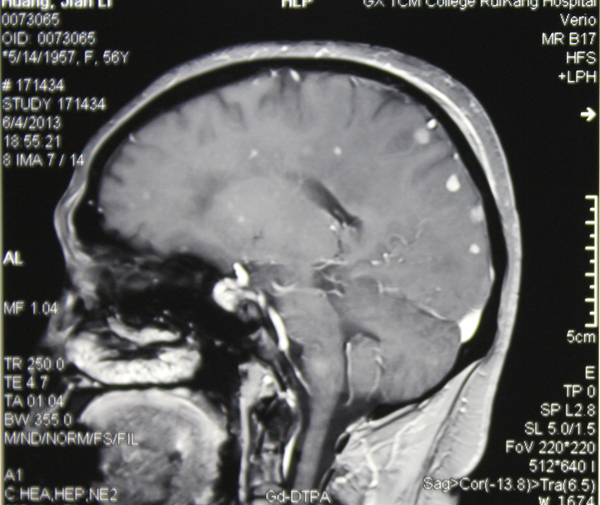

按照抗真菌治疗一个月后,黄阿姨已经能下床走路了,说话变清楚了,看到女儿也乐呵地笑了。6月18日,黄阿姨在家人的陪伴下康复出院了。

治疗一个月后,大部分感染已消失或缩小。